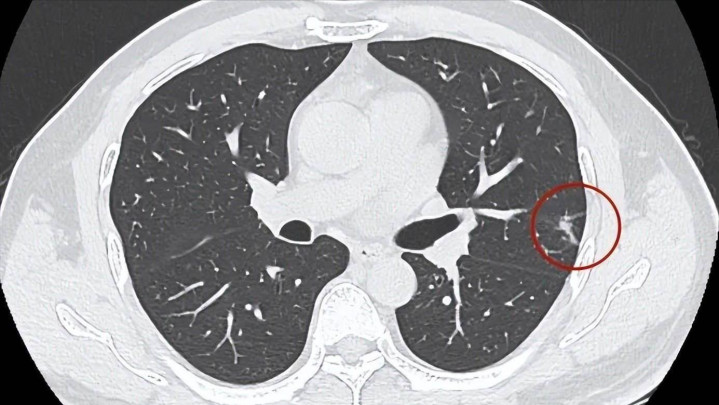

“身体检查一切正常,结果却查出肺结节?”

不少人走进诊室时,一脸疑惑或焦虑,仿佛肺结节成了悬在头上的“达摩克利斯之剑”。

肺结节并没那么可怕,真正需要警惕的,是术后该注意却不注意的那些“坑”。做过肺结节切除手术的朋友,千万别以为手术是终点,恰恰它只是新的起点。

肺结节的性质,有可能随着时间和环境改变而发生转变。比如亚实性结节,在早期可能是良性的炎性病灶,但有部分会演变为不典型腺瘤样增生,甚至发展为早期肺癌。